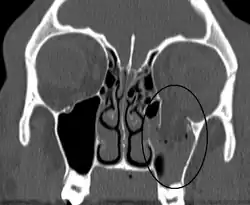

Orbital blowout fracture

| An orbital blowout fracture of the floor of the left orbit. | |

An orbital blowout fracture is a traumatic deformity of the orbital floor or medial wall that typically results from the impact of a blunt object larger than the orbital aperture, or eye socket.[1] Most commonly this results in a herniation of orbital contents through the orbital fractures.[1] The proximity of maxillary and ethmoidal sinus increases the susceptibility of the floor and medial wall for the orbital blowout fracture in these anatomical sites.[2] Most commonly, the inferior orbital wall, or the floor, is likely to collapse, because the bones of the roof and lateral walls are robust.[2] Although the bone forming the medial wall is the thinnest, it is buttressed by the bone separating the ethmoidal air cells.[2] The comparatively thin bone of the floor of the orbit and roof of the maxillary sinus has no support and so the inferior wall collapses mostly. Therefore, medial wall blowout fractures are the second-most common, and superior wall, or roof and lateral wall, blowout fractures are uncommon and rare, respectively. They are characterized by double vision, sunken ocular globes, and loss of sensation of the cheek and upper gums from infraorbital nerve injury.[3]

Thin cut (2-3mm) CT scan with axial and coronal view is the optimal study of choice for orbital fractures.[16][17]

Plain radiographs, on the other hand, do not have the sensitively capture blowout fractures.[18] On Water's view radiograph, polypoid mass can be observed hanging from the floor into the maxillary antrum, classically known as teardrop sign, as it usually is in shape of a teardrop. This polypoid mass consists of herniated orbital contents, periorbital fat and inferior rectus muscle. The affected sinus is partially opacified on radiograph. Air-fluid level in maxillary sinus may sometimes be seen due to presence of blood. Lucency in orbits (on a radiograph) usually indicate orbital emphysema.[4]